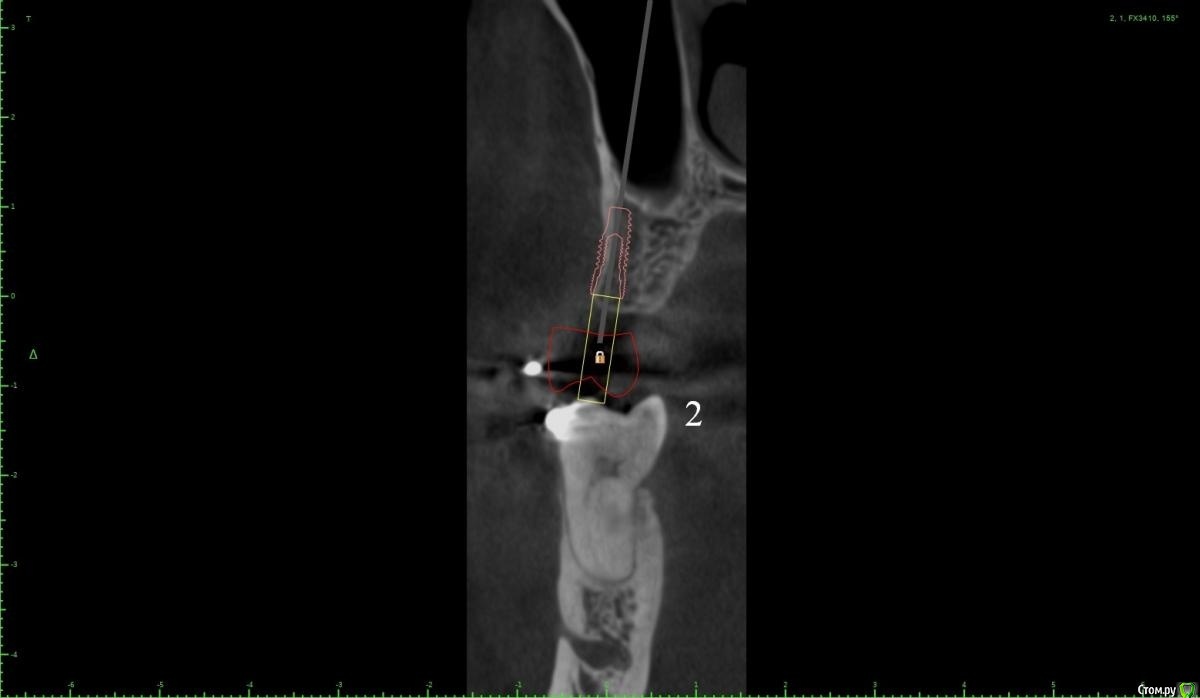

Женька Опубликовано 18 января, 2021 Поделиться Опубликовано 18 января, 2021 (изменено) Коллеги, здравствуйте!Вот такой пациент после орто. Дуги пока на месте, думаем не снимать в области отсутствующих зубов с целью удержать место до этапа протезирования.Вопрос касаемо верхнего винта.Правильно ли я понимаю, что правильным будет именно положение под цифрой 2? Хочу попробовать титановый смарт билдер, как по мне дефект как раз подходит. Или лучше мини сосиску и отсрочено в регенерат ставить. Что думаете? p.s что сверху, что снизу шестые требуют покрытия коронок, отсюда еще один вопрос, стоит ли просить ортодонта стараться ещё ангулировать 46? Просто побаиваюсь, что без этой ангуляции (если ортодонт скажет фи), не удастся сохранить зуб витальным. Ну и бонусом будет поднутрение, не получится адекватно сделать коронку и будет треугольник с едой в этой области. Изменено 18 января, 2021 пользователем Женька Ссылка на комментарий